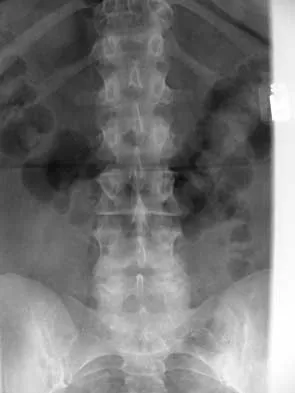

A 44-year-old woman has had lower extremity dysesthesias, urinary incontinence, and has been unable to walk for the past 2 days. She reports no pain or history of trauma. She notes that 3 weeks ago she missed work for 2 days because of back pain, but it resolved with rest. Examination shows decreased or absent sensation below the knees, no motor function below the knees, and decreased rectal tone. Catheterization results in a postvoid residual of 2,000 mL. Plain radiographs and MRI scans without contrast are shown in Figures 1a through 1d. What is the next most appropriate step in management?

Explanation

The patient has had a clear and sudden onset of a profound neurologic deficit. The radiographic studies suggest a lesion in the conus medullaris that appears to be intradural and intramedullary. MRI, with and without contrast, will best evaluate this mass further. The addition of gadolinium allows further evaluation of vascularity and the extent of the lesion. Eichler ME, Dacey RG: Intramedullary spinal cord tumors, in Bridwell KH, Dewald RL (eds): The Textbook of Spine Surgery, ed 2. Philadelphia, PA, Lippincott-Raven, 1997, vol 2, pp 2089-2116.